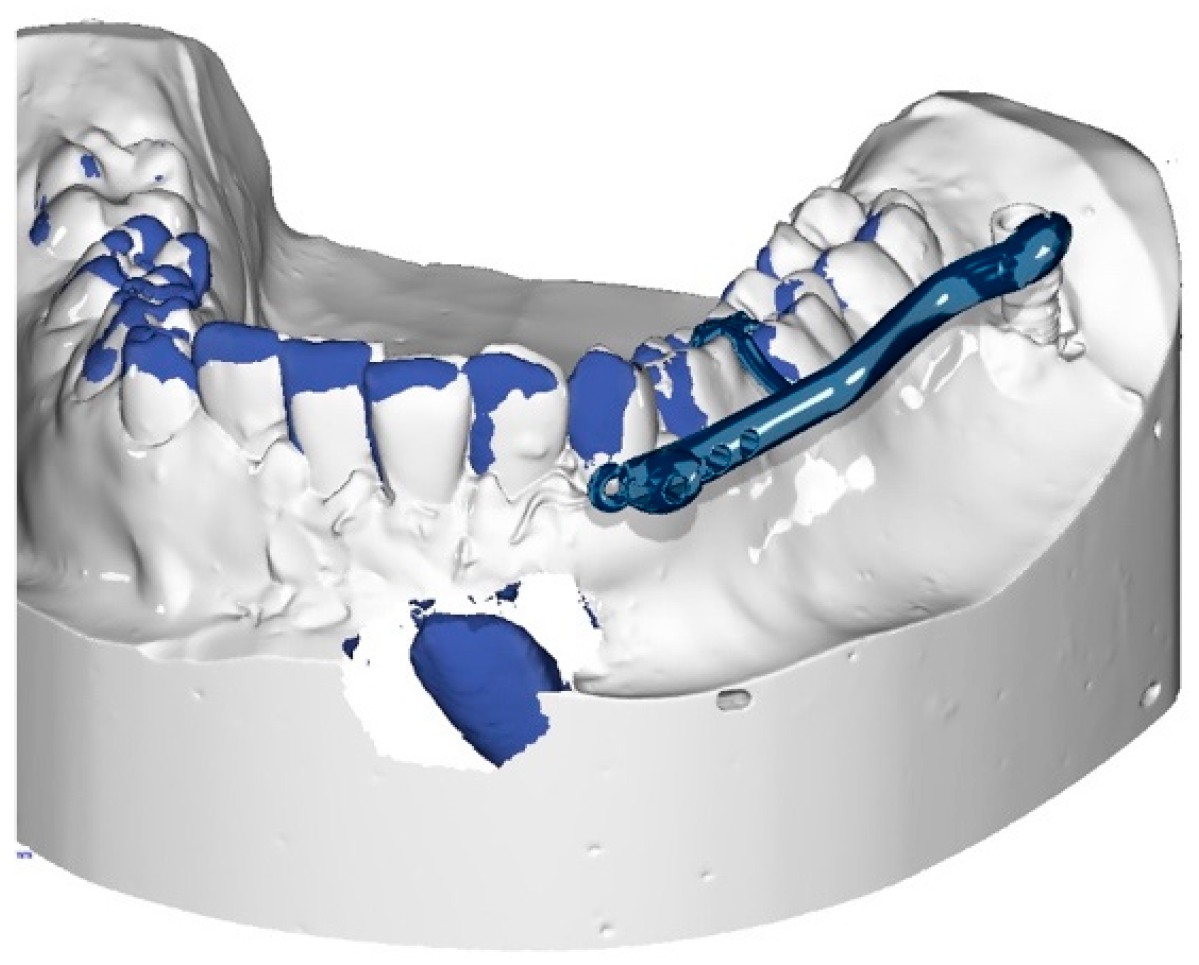

The procedure and potential risks associated with canine disimpaction, with particular emphasis on the risk of root resorption to adjacent elements, were fully explained to the subject and parents and signed informed consent for the publication of images and data was obtained. The disimpaction treatment consisted of a surgical phase of exposure of the impacted canine, with the possible removal of eruptive obstructions, and an orthodontic traction phase performed with a custom-made skeletal and dental anchorage device. The miniscrew insertion sites were planned on 3D images generated by merging CBCT and digital dental model images. The TADmatch 3D module of the Onyxceph3™ software (Image Instruments, Chemnitz, Germany) was used for the computer-guided planning of screw insertion using a surgical guide (Figure 5). A CAD/CAM digital workflow was performed to design the surgical guide and the skeletal anchoring disimpaction device using the Ortho Apps 3D module of the Onyxceph3™ software 3.2.180 Build 492–K2 (Image Instruments, Chemnitz, Germany) (Figure 6). The surgical guides were fabricated using TruPrint 1000 (TRUMPF Homberger S.r.l, Buccinasco, Italy) and the disimpaction device by laser melting technology with cobalt chrome metal powder (Stratasys OrhoDesktop; Stratasys, Rehovot, Israel) (Figure 7).

Figure 6. Planning of the customized skeletally anchored device in the three-dimensional (3D) digital model of the lower arch.